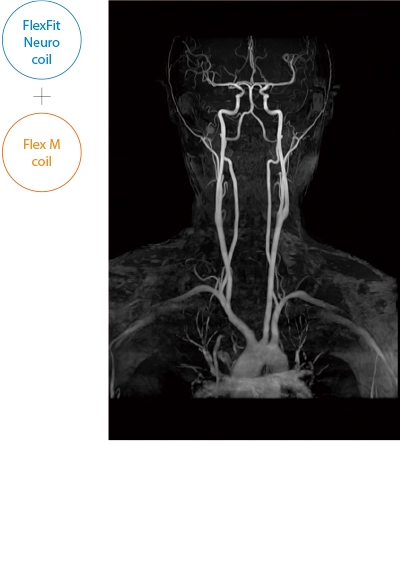

The ECHELON Synergy ZeroHelium is equipped with a flexible head and neck coil that allows one-action setup via sliding installation, as well as a Flex coil that provides wide and flexible coverage of the imaging area. This enables flexible adaptation to different part of body.

After the completion of MRA imaging, it automatically performs clipping for cerebral MRA. The automatic clipping identifies the extraction range based on the characteristics of the head. Additional clipping can also be performed on the images after the automatic clipping process.